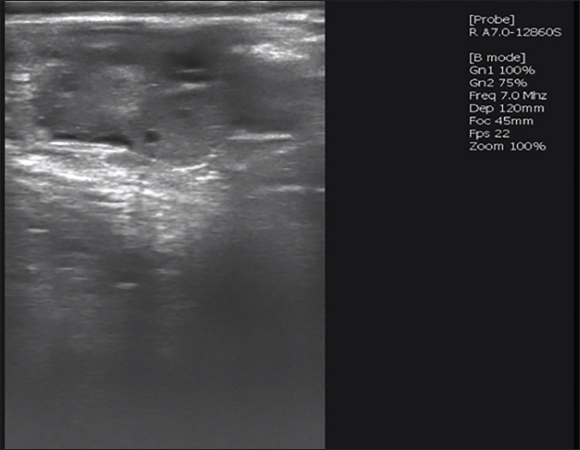

Insemination and embryo collection

Fig. 3. CL of superovulation results using ultrasound.